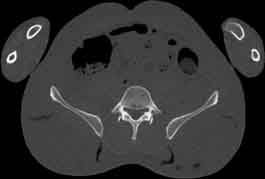

Visible Human male: Sectio transversalis 1752

CT